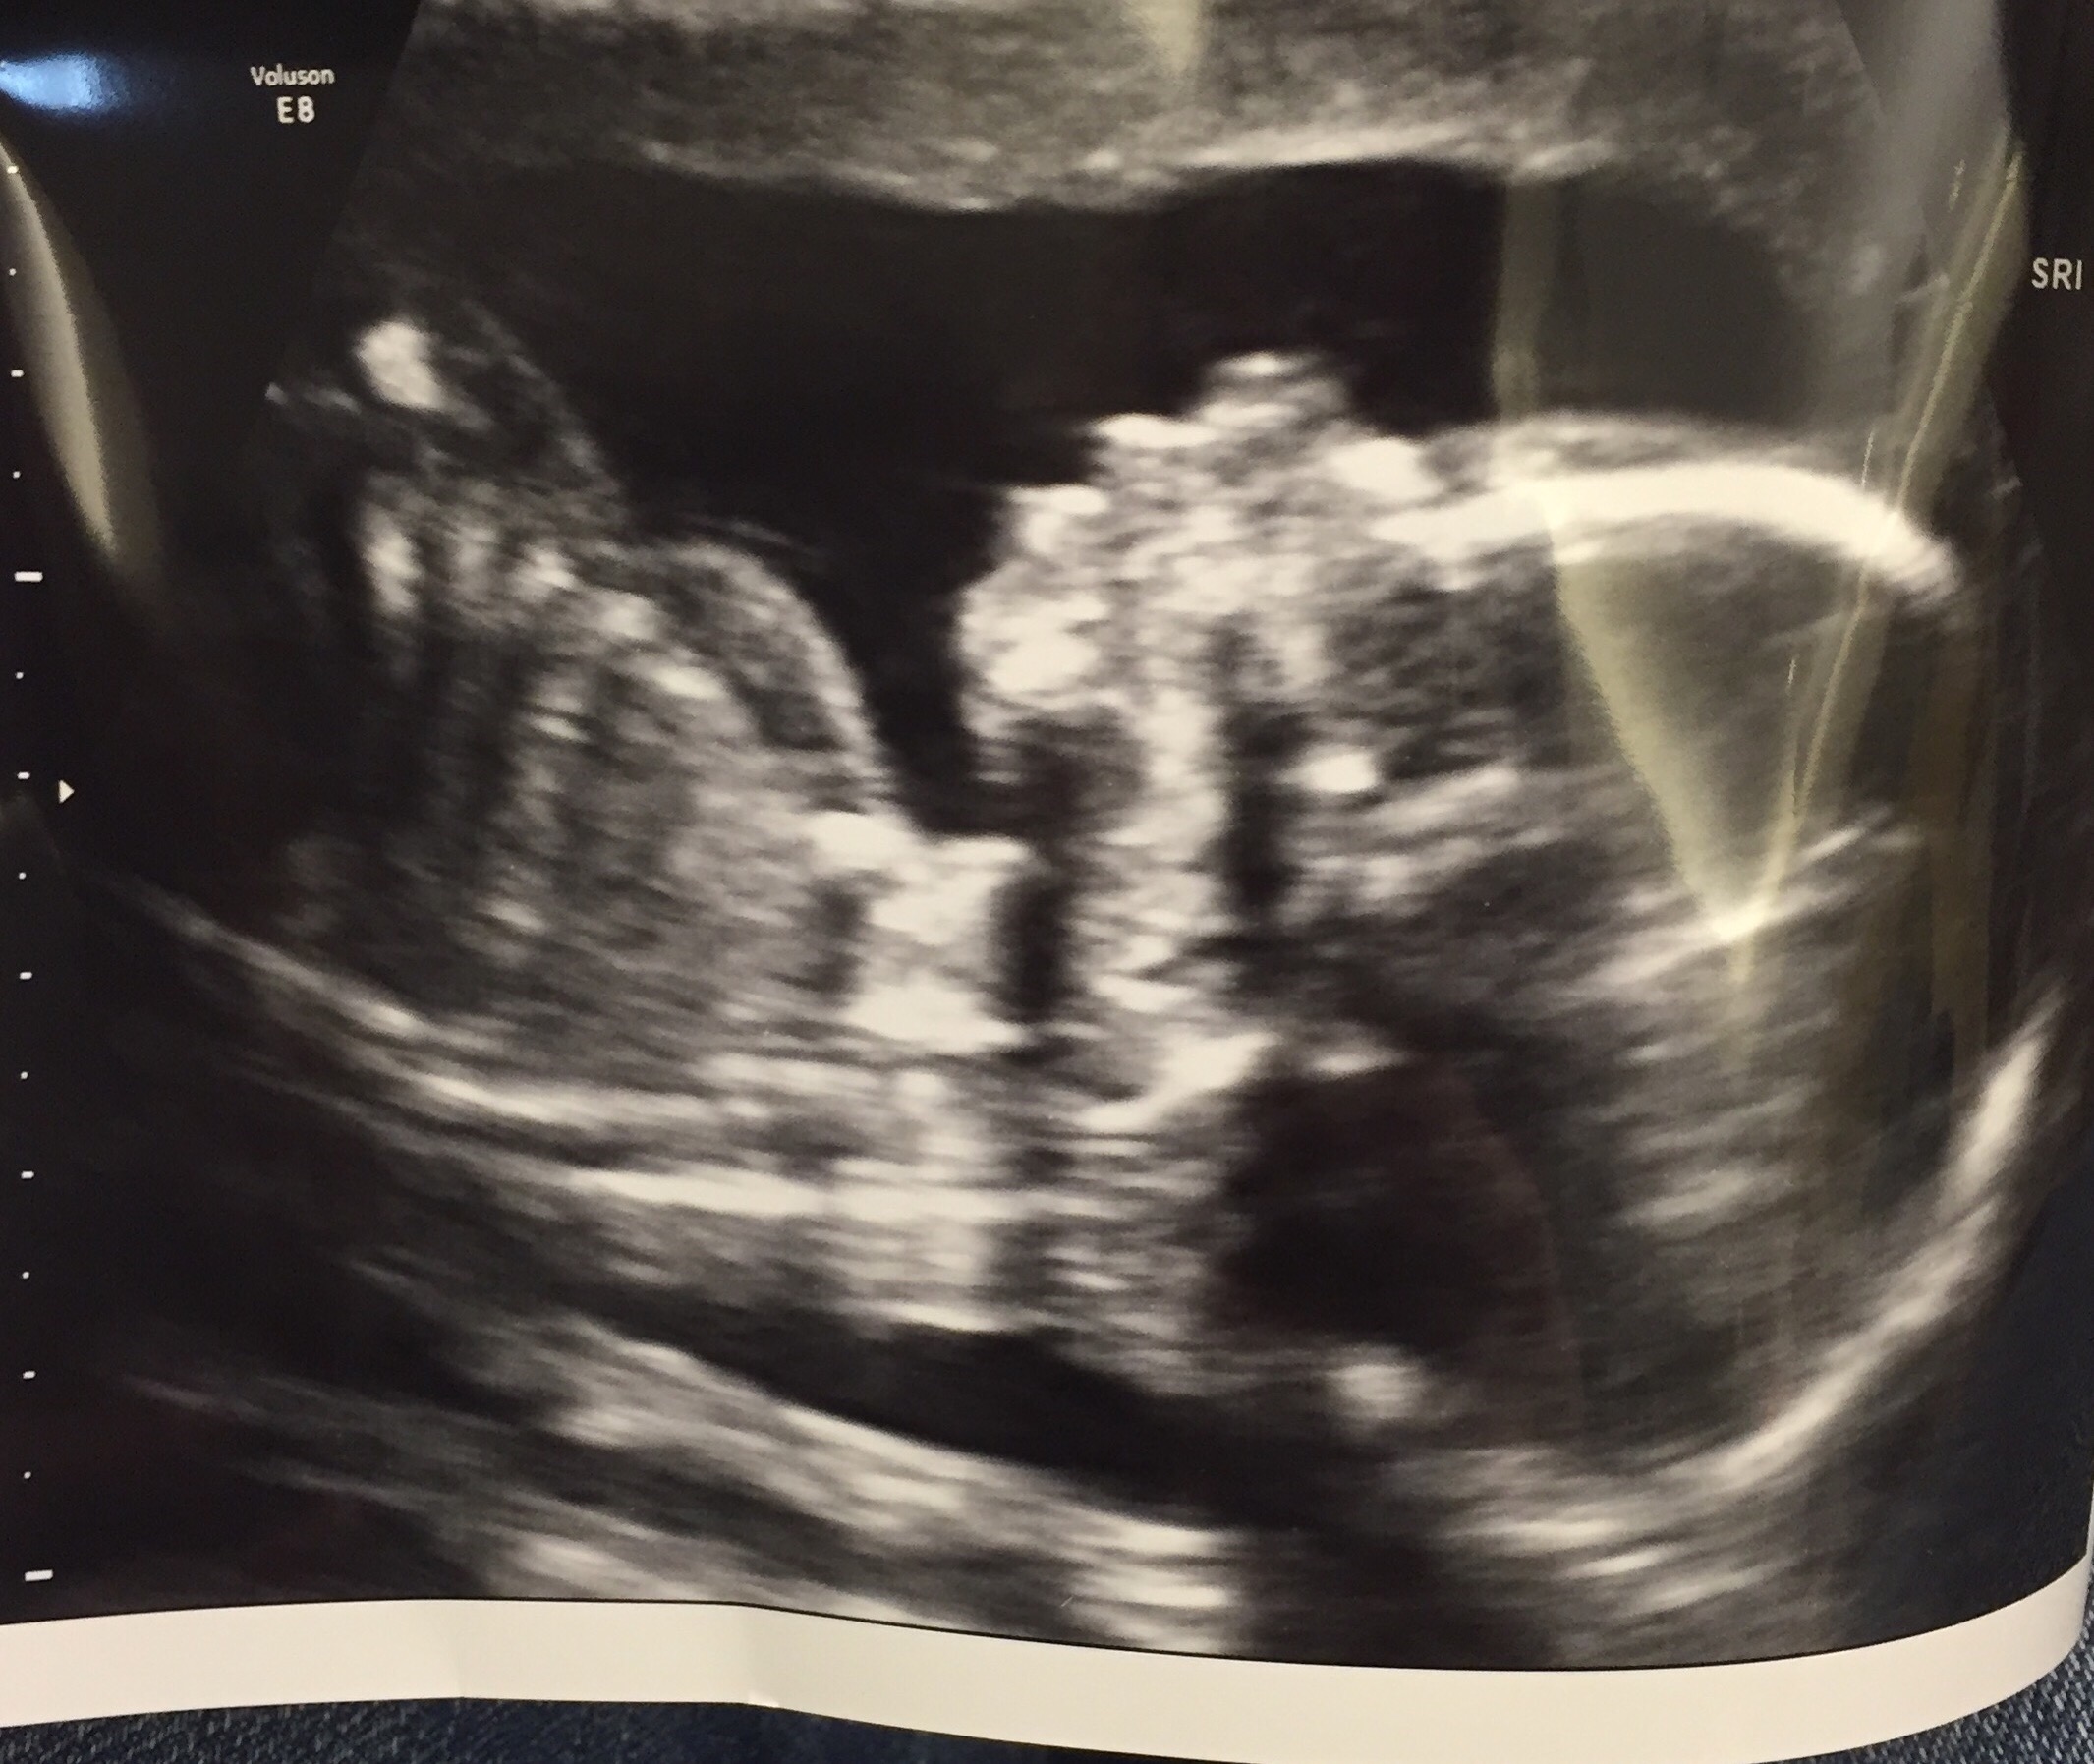

However, on January 11th at 8:34pm we received the call we had been waiting for. Baby girl Cardoso was healthy! I thought, “It’s really happening this time. We are actually going to have a baby.” David and I hugged each other so tight and I of course cried tears of pure joy. I couldn’t wait to share the happy news and began to make phone calls the next day to family and shared the news on social media with friends. My next ultrasound was the following week with my primary OB and this was the first time I allowed myself to connect to the baby on the screen. A tear rolled down my cheek as I watched her wiggle around and move her arms and legs. I can’t stop resting my hand on my tummy, and every now and then I’ll feel her kick to let me know everything is ok in there. Oh it’s all just so surreal.